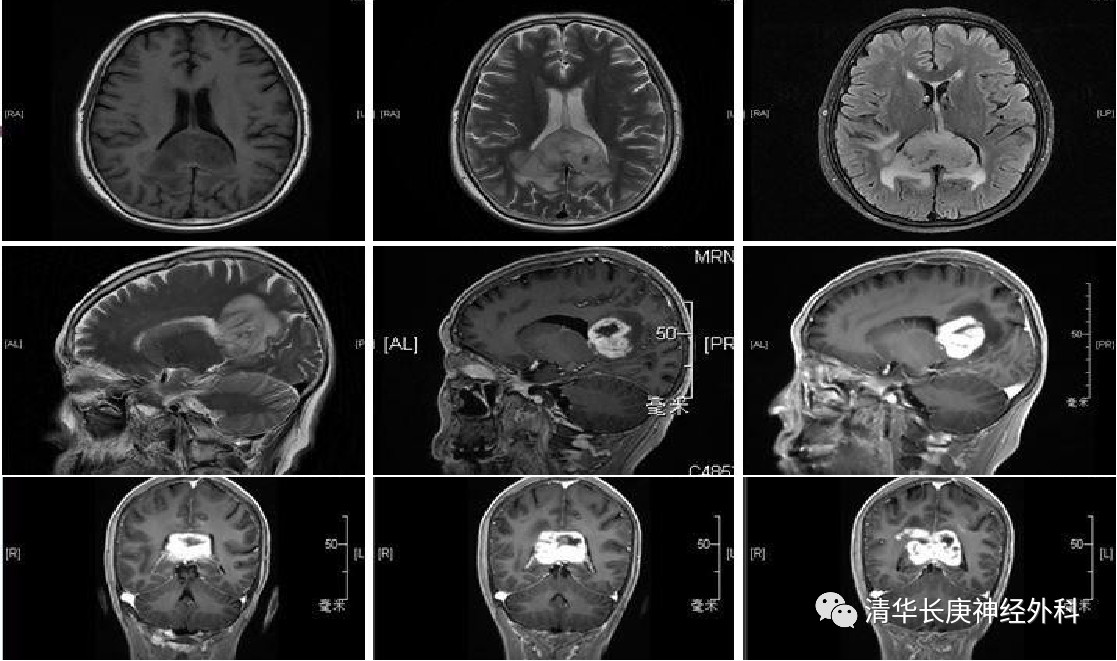

2020 年 3 月,河北省 70 多岁的尹奶奶在 1  个月前发现咽喉部有异物感,吞咽时困难,并且时常对刚刚发生的事记不起来。就诊于当地医院行 MRI 检查,提示胼胝体压部巨大异常信号影,辗转多家医院,根据多位专家的经验,恶性肿瘤的可能性很大,已经失去手术的机会了。患者来到神经外科王贵怀主任的门诊时,要求很明确,希望通过手术机器人技术,仅取病变活检,进一步测序以便选择化疗药物进行后续治疗。王主任认真评估了患者的情况,考虑到病变位置深,临近周围多个重要神经核团,病变内存在坏死的空洞, 穿刺活检也存在不小的风险和难度。(图 2)

图 2 术前增强MRI 脑深部功能区巨大肿瘤,胼胝体压部,右颞叶内侧巨大异常信号影,恶性胶质瘤可能性大